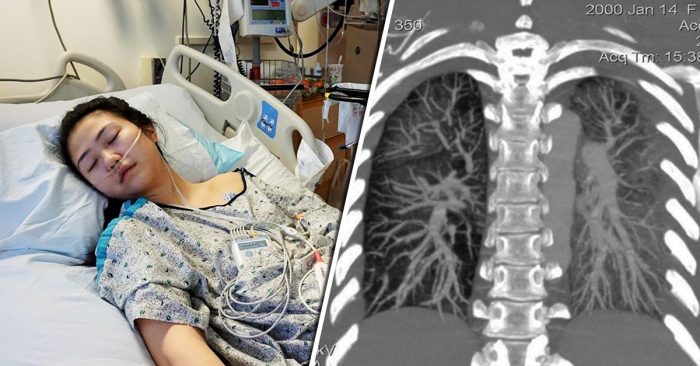

Seorang remaja wanita dari Maryland, Amerika Syarikat baru-baru ini berkongsi sekeping gambarnya yang sedang terlantar di katil hospital hanya disebabkan oleh penggunaan rokok elektronik.

Wanita berkenaan, Claire menulis di laman sosialnya bahawa walaupun kemungkinan selepas ini nyawanya berjaya diselamatkan, namun katanya, keadaan paru-parunya tetap akan rosak selamanya.

Berikutan itu, Claire sekali lagi memuat naik gambar yang menunjukkan imbasan sinar x pada paru-parunya yang kelihatan berkabus. Menerusi gambar imbasan paru-paru berkenaan, dapat dilihat bahawa kedua-dua belah paru-parunya kelihatan seperti berkabus, yang mana sepatutnya organ paru-paru yang sihat akan kelihatan jelas dalam imbasan.

Claire menulis bahawa mungkin kiriman itu adalah kirimannya yang terakhir, dan mengatakan bahawa sebelum dia mengambil rokok elektronik, dia tidak pernah mengalami batuk, sakit dada dan kesukaran untuk bernafas.